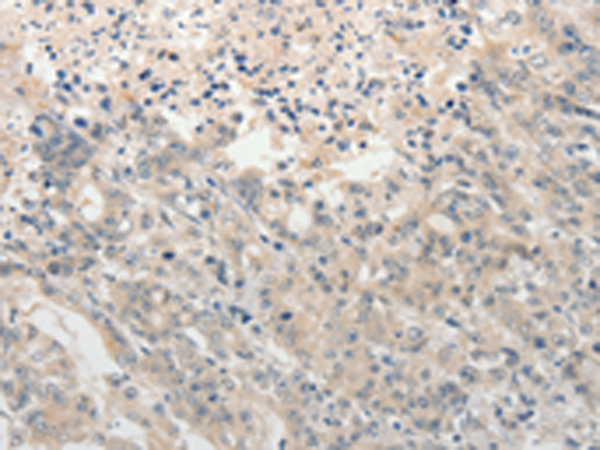

分类: 科研抗体货号: P11172别名:应用: IHC反应种属: Human, Mouse

分类: 科研抗体货号: P11170别名: PAQR2; ACDCR2应用: IHC反应种属: Human, Mouse

分类: 科研抗体货号: P11167别名: DSH; AGS6; G1P1; IFI4; P136; ADAR1; DRADA; DSRAD; IFI-4; K88DSRBP应用: IHC反应种属: Human

分类: 科研抗体货号: P11175别名:应用: IHC反应种属: Human

分类: 科研抗体货号: P11187别名: ANKRA应用: IHC反应种属: Human, Mouse

分类: 科研抗体货号: P11166别名: ADAM-TS6; ADAMTS-6; ADAM-TS 6应用: IHC反应种属: Human

分类: 科研抗体货号: P11174别名: AYTL3; AGPAT7; LPEAT2; LPAAT-eta应用: WB,IHC反应种属: Human, Mouse

分类: 科研抗体货号: P11186别名:应用: IHC反应种属: Human